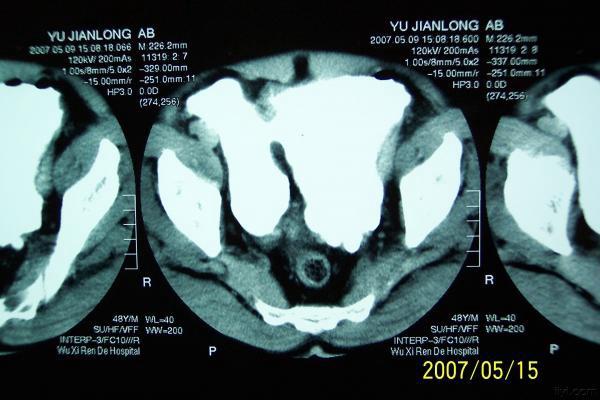

分享下一例巨大膀胱憩室的图片

分享下一例罕见病历的图片,这是我遇到的最大巨大膀胱憩室。

双膀胱,少见,要看输尿管注入膀胱的位置。

考虑双膀胱的可能性大.

双膀胱畸形